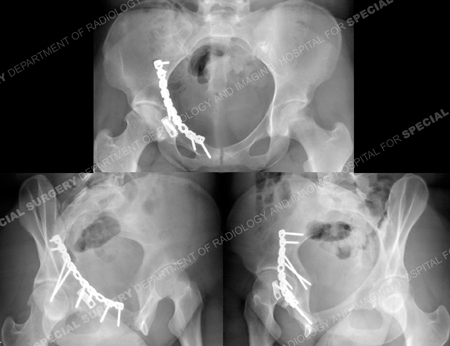

A 13-year-old girl fell while skiing and was taken to a local hospital. Radiographs were obtained and revealed a right-sided Anterior Column with Posterior Hemi Transverse acetabular fracture. She was placed in skeletal traction and transferred to the care of

Dr. David L. Helfet at Hospital for Special Surgery's Orthopedic Trauma Service for definitive management of her acetabular fracture. Open reduction and internal fixation was performed with placement of contoured plates and screws. She returned for regular follow-up visits and healed uneventfully and at her most recent follow-up visit at 8.5 years following surgery she has excellent clinical and radiographic results and reported complete resolution of pain with full range of motion in the hip joint.

Fracture surgery was performed using an ilioinguinal approach. The fracture was reduced and stabilized using a contoured 10-hole pelvic reconstruction plate and screws and placement of a spring plate along the anterior wall fracture. Postoperative CT scan images (right images) illustrate an adequate reduction.

The patient returned at 8.5 years following surgery and radiographs demonstrate a healed acetabular fracture and maintenance of joint space. She had fully returned to full activities and reported no pain.